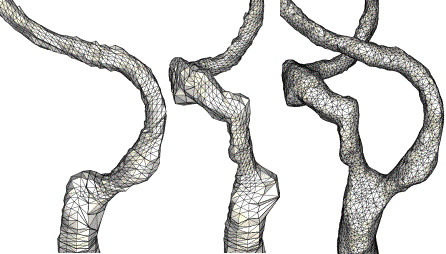

The second case corresponds to the reconstruction of the carotid

bifurcation from contrast-enhanced MRA images of a patient

with atherosclerosis. As in the previous case, deformable

models were used to reconstruct each arterial branch independently

in order to avoid intersections with other close vessels present

in the images. These branches were then merged into a watertight

model and used as a support surface to generate a finite element

grid with a uniform element size distribution. The MIP of

the anatomical images is shown in Fig. 2a, the reconstructed

model of the right carotid artery is shown in Fig. 2b and

the surface of the final finite element grid is shown in Fig.

2c.

Figure 2. Construction

of realistic carotid bifurcation model from MRA images of

a patient with atherosclerosis: a) MIP projection of the

contrast-enhanced MRA images; b) reconstructed model of

the right carotid artery; c) surface of the final finite

element grid.

A detail of the reconstructed models of the ICA and ECA

extending into the CCA are shown in Fig. 3a and 3b, respectively.

The surface triangulation of the bifurcation model after

merging the ICA and ECA models is shown in Fig. 3c.

Figure 3. Merging

models of the ICA and ECA extending into the CCA in order

to create a watertight model of the carotid bifurcation:

a) model of the ICA; b) model of the ECA; c) merged bifurcation

model.